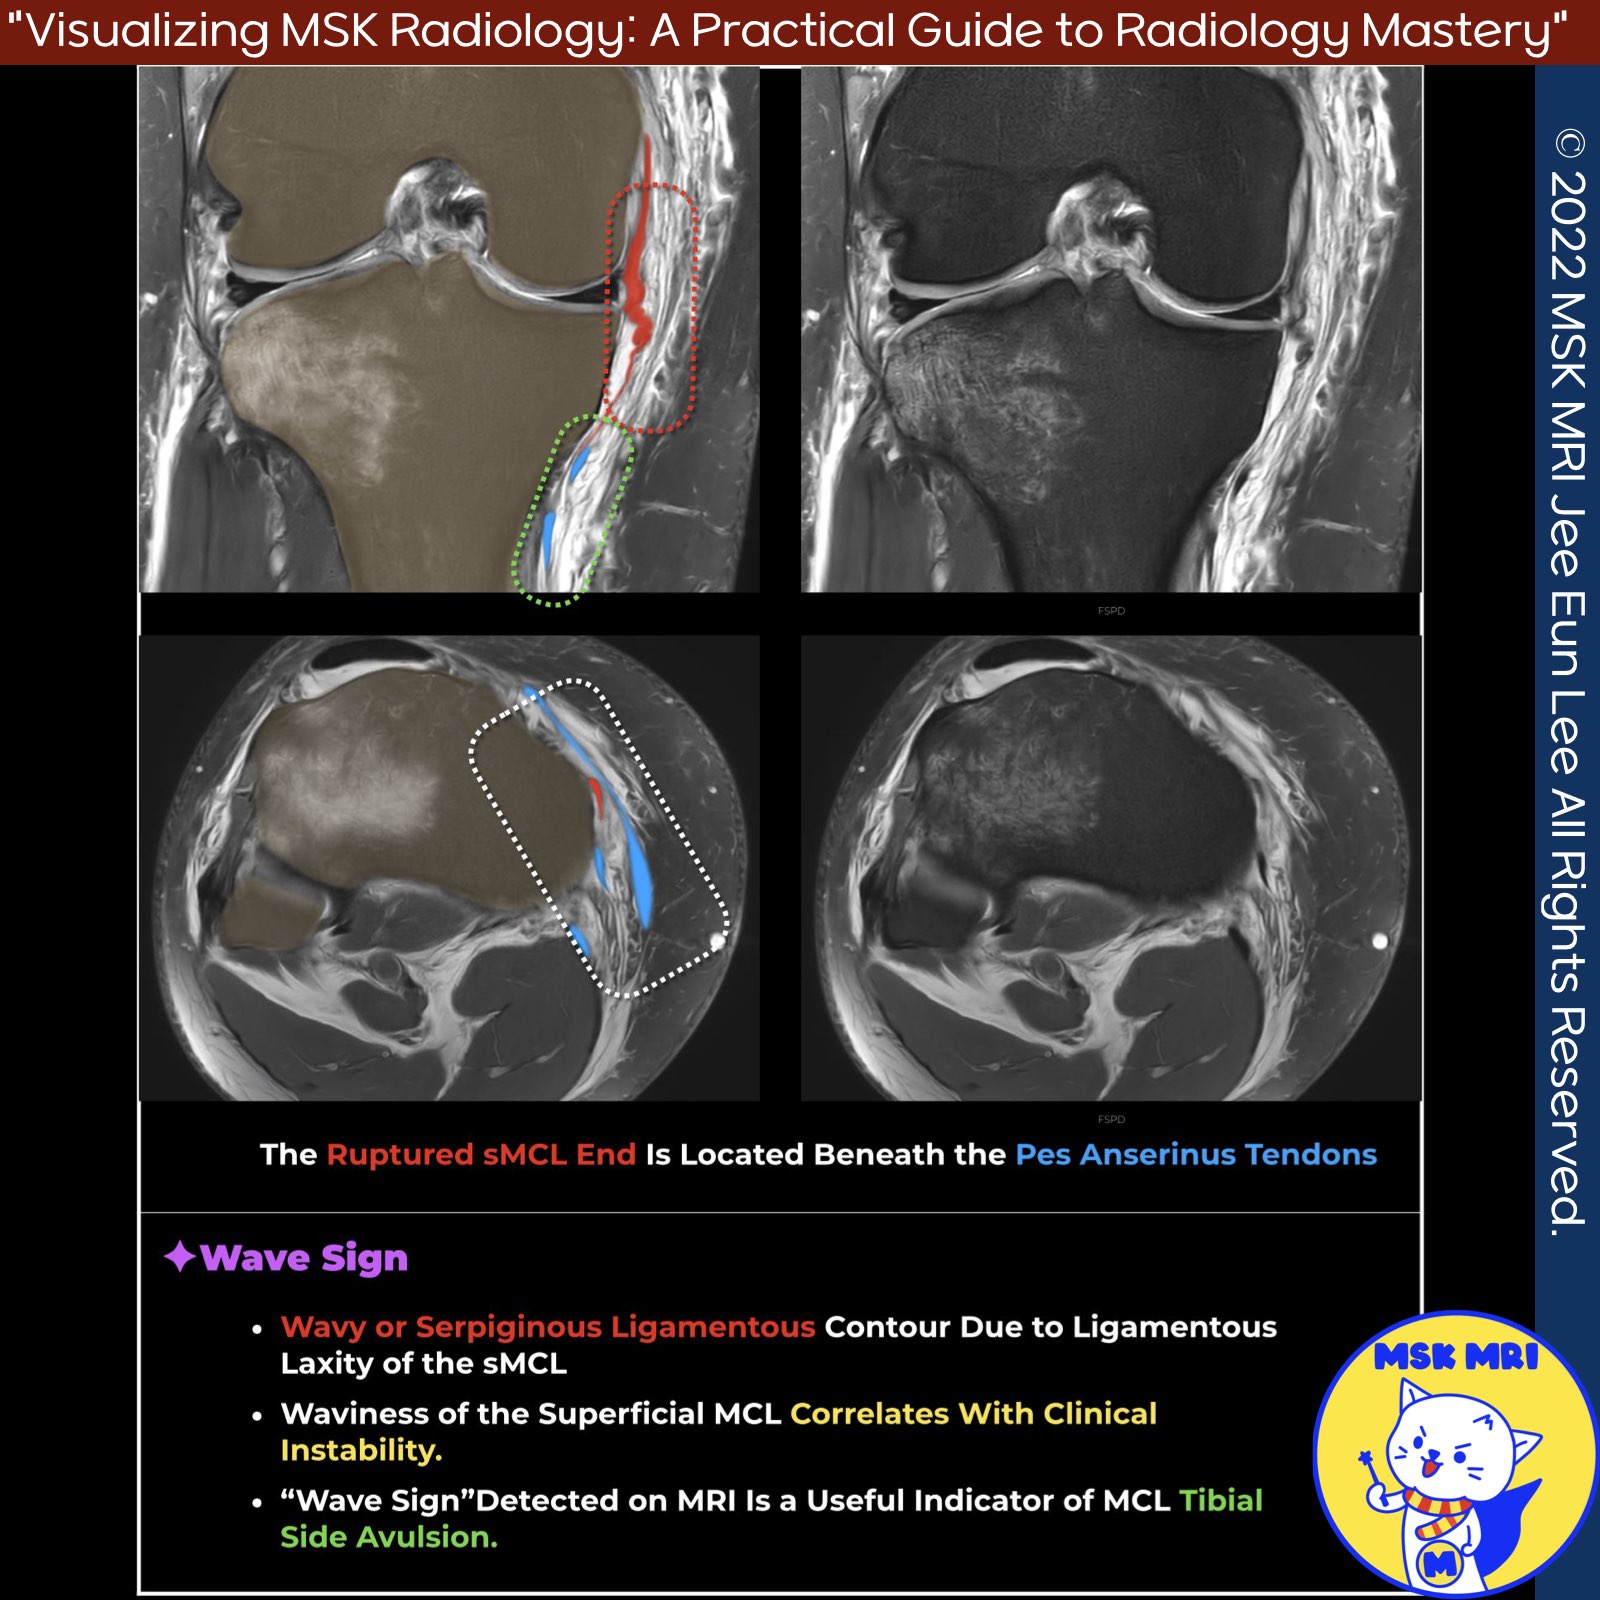

📌 The Wave Sign: Tears of the Distal Superficial Medial Collateral Ligament

- Tears of the superficial medial collateral ligament (sMCL) most commonly involve the proximal or middle portion.

- The "wave sign" on MRI is essential for diagnosing medial collateral ligament tibial side avulsions.

- Waviness of the superficial MCL and injuries to other structures like the deep MCL, ACL, and posteromedial corner correlate with clinical instability.

✅ Differentiating from Pes Anserine Bursitis

- Edema near the distal attachment of the sMCL should be carefully inspected, as distal sMCL injuries may simulate pes anserine bursitis.

- In pes anserine bursitis, the pes bursa is distended superficial to the MCL and deep to the pes anserinus tendons at the level of the proximal tibia, while the superficial MCL appears normal.

✅ Non-Stener-like Lesion

- Axial images should be examined carefully to determine if a Stener-like lesion has occurred.

- In a non-Stener-like lesion, the torn retracted ligament fibers of the distal superficial MCL remain deep to the pes anserinus tendons.